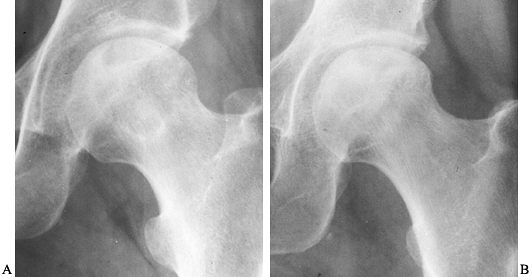

Figure 125.11. Stage II osteonecrosis showing areas of sclerosis and radiolucency within the femoral head.

|

Figure 125.12. Stage III osteonecrosis. Note the crescent sign, indicating subchondral collapse without flattening of the articular surface.

Figure 125.13.

Stage IV osteonecrosis. Marked flattening of the femoral head is present without radiographic evidence of acetabular involvement. |

Figure 125.14.

Stage V osteonecrosis. The femoral head is markedly flattened. The joint line is narrowed, and the acetabulum shows irregularity, sclerosis, and radiolucency. |

Figure 125.15.

Stage VI osteonecrosis showing advanced degenerative changes that have taken place in the hip joint secondary to osteonecrosis of the femoral head, treated by intertrochanteric osteotomy. |